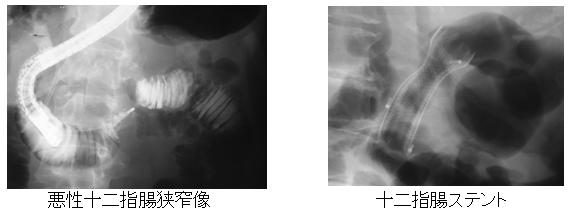

6.悪性十二指腸狭窄に対するステント留置

胃癌、十二指腸癌、膵・胆道癌では時に十二指腸に直接浸潤し、十二指腸内腔が狭窄ないし閉塞して食事が通らなくなってしまうことがあります。そのような場合、以前では全身麻酔下に開腹手術を行い胃と空腸のバイパスを作製する必要がありました。しかし、近年では内視鏡的に金属の網でできた太いパイプ状のステントを十二指腸内腔に留置することにより、狭窄部を拡げてまた食事ができるようにすることが可能となりました。適応症例を選ぶことにより良好なQuality of Lifeを実現することができます。